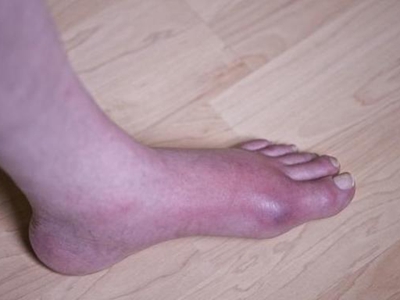

痛风急性发作时,表现为关节红肿、灼痛、感觉过敏、活动受限,伴畏寒、发热、头痛、乏力和纳差等症状。常于夜间发作,白天缓解,入夜又发,经几日到几周发作而逐渐停止,关节疼痛缓解。